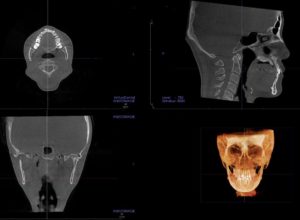

CT撮影

歯や顎の骨の状態を確認します。